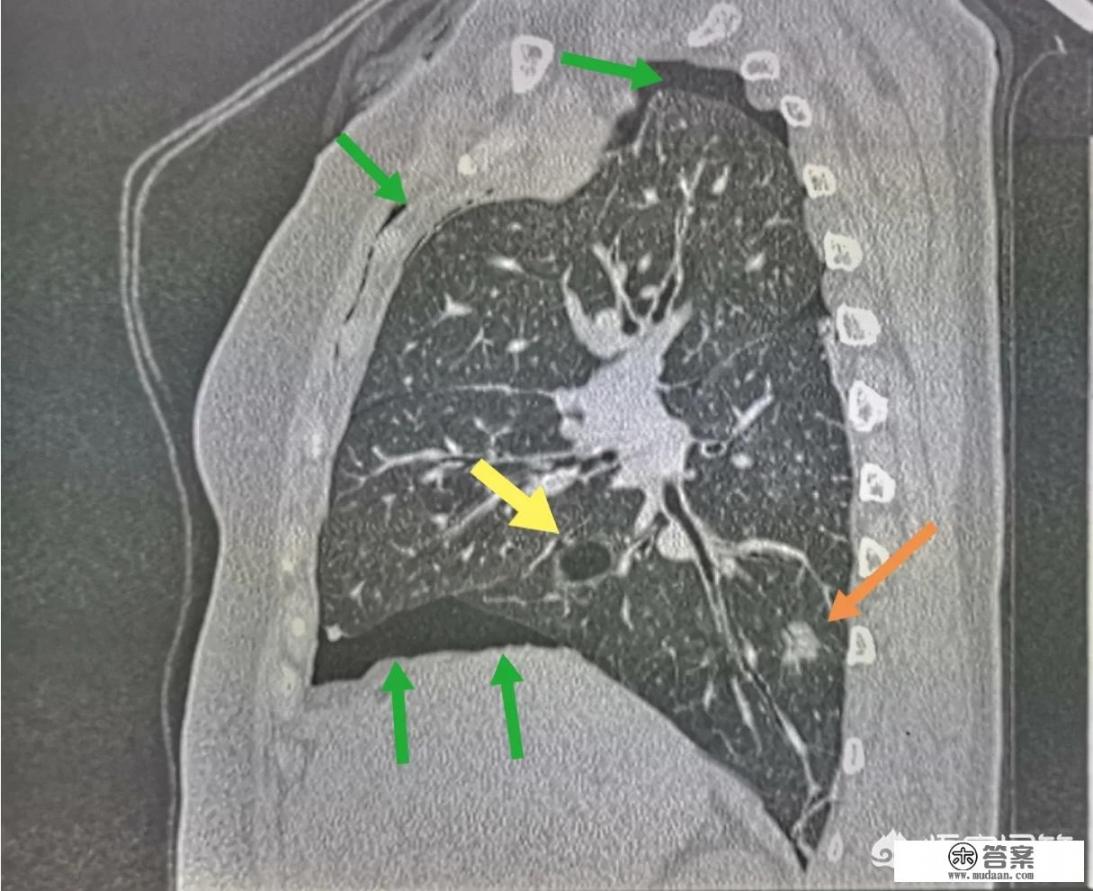

气胸的成因复杂多样,但其中最引人注目的是其与体型和肺部健康状况的紧密联系,正如前文所述,瘦高体型的年轻人因肺部与肋骨间的脂肪缓冲较少,在剧烈运动或提重物时容易发生气胸,肺部的原发性疾病如慢支、肺气肿、肺结核等也是导致气胸的重要因素,这些疾病常伴随肺大泡的形成,一旦肺大泡破裂,气体进入胸膜腔,就会引发气胸。

气胸的治疗方法根据病情的严重程度和患者的具体情况而异,对于轻度气胸且症状不明显的患者,卧床休息和氧疗是首选方法,而中重度气胸,特别是肺部压缩超过30%且伴有明显症状的患者,则需进行胸膜腔穿刺或胸腔闭式引流术以帮助排气,对于反复发作或伴有其他并发症的气胸患者,胸腔镜微创手术是一个有效的治疗选择,不仅能恢复肺功能,还能减少复发的风险。